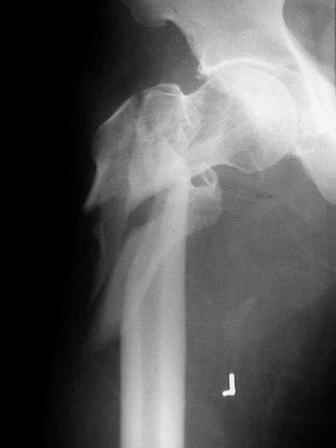

Few days ago I have posted an x-ray of severely comminuted Trochenteric # of Lt. Femur with sub-trochenteric extension of a male patient aged 65 years for opinion of fixation. Eight of you have kindly replied........

I choose Long Gamma Nailing and did it on 24.1.2006.

Now posting the post op x-rays for all of yours comments please. Don't hesitate to criticize me.

Congratulations. Virtually perfect. What reduction technique did you use? Looks like still traction table? To cavil to at least something looks like reduction is in microscopic varus - comparative x-rays can clear this - though only for academic interest with no clinical significance. Did you insert distal screws?